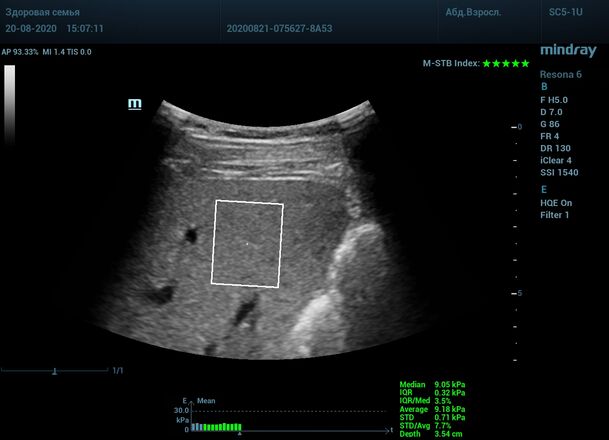

Как работает эластография сдвиговой волны? Датчик посылает плотный пучок ультразвуковых волн в ткани, ткани сжимаются, а затем возвращаются в исходное состояние за счет своей эластичности. Расправление ткани создают поперечные ультразвуковые волны, которые регистрируются трансдьюссером. Прибор во время исследования непрерывно отображает график значений плотности печени (kPa) в исследуемой зоне, достоверным считается график в виде прямой линии. Такая линия формируется путем получения близких по значению показателей. Количественным показателем является отношение межквартального интервала к медиане (IQR/Med). Допустимым считается результат с IQR/Med менее 30%. Чем данный показатель меньше, тем более точным является исследование. Для достоверного исследования в идеале нужно 10 значений.

3. - Неподвижная печень. Достигается путем задержки дыхания на выдохе. Выдох позволяет уменьшить давление на печень органами грудной клетки и брюшной полости. Задержка дыхания останавливает её. Критерием качества является индекс M-STB, выраженным в количестве звезд. Прибор определяет его автоматически. 4-5 звезд индекса свидетельствует о неподвижной печени.

Приводим видео пример: использованы 3 точки доступа печени, каждое значение графика получено прицельным выстрелом HQ Elasto и собрано в единый тренд. В результате анализа 10 значений получен удивительно точный результат - статистический разброс  3.5 % IQR/Med.